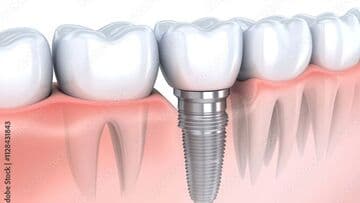

インプラントは、失った歯の部位に人工歯根を埋入し上部に人工歯を装着することで、天然歯のようにものを噛んだり、見た目を美しくすることができます。今後インプラント治療をお考えの方は、まずは、インプラントの特性を知るために、インプラントの構造や具体的なメリット・デメリットを把握する必要があると考えます。そして、ご自身の今後の治療の選択や、インプラントを埋入した後の日々のメンテナンスにその知識を役立ててもらえればと思います。

インプラントの構造について

インプラントと天然歯は、見た目は似ていますが、構造的には大きな違いがあります。インプラントは人工的に歯の機能を再現したものであり、天然歯とは異なる構造を持っています。

天然歯は歯髄や歯根膜に神経が通っており、温度や圧力を感じ取ることができます。しかし、インプラントには神経や歯根膜がないため感覚が鈍く、強く噛みすぎても気づきにくい、物を噛んだ時に硬い感じがするなどという感覚の違いがあります。強すぎる力がかかると、骨の吸収(骨が減る)などにつながるリスクがあるため、定期的に適切な管理が必要です。